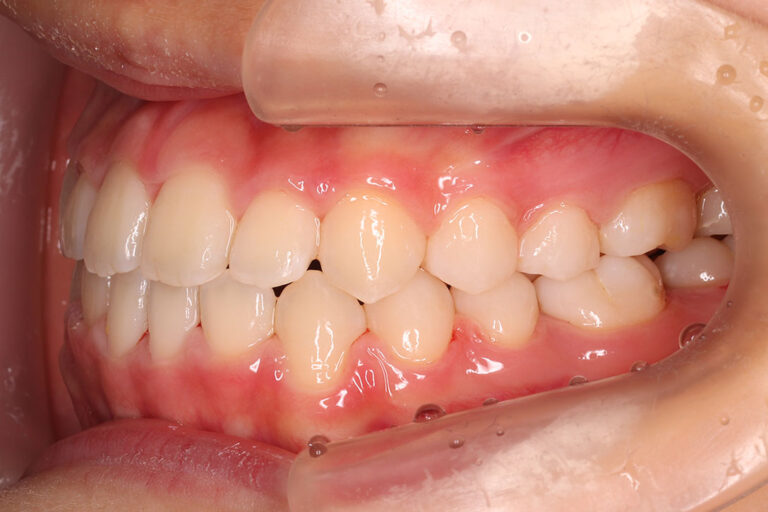

| 小児矯正から始められた受け口傾向の患者さんです。

前歯が反対咬合で、永久歯の萌出スペース不足による上顎前歯部の叢生(がたつき)が予測できる患者さん。 骨格的に、上顎と比べ下顎が大きく、成長によっては外科手術になる可能性もありましたが、 外科手術はせず、矯正治療のみで咬み合わせを改善しています。 小児矯正で、前歯部の被蓋(重なり)の改善まで治療を行い、下顎の成長を観察した後に、 永久歯列から、マルチブラケット装置により非抜歯にて配列しました。 来院間隔1.5カ月でしたが、平均より短く治療を終えることが出来ました。 マルチブラケット 動的治療期間 2年1か月 調整回数14回